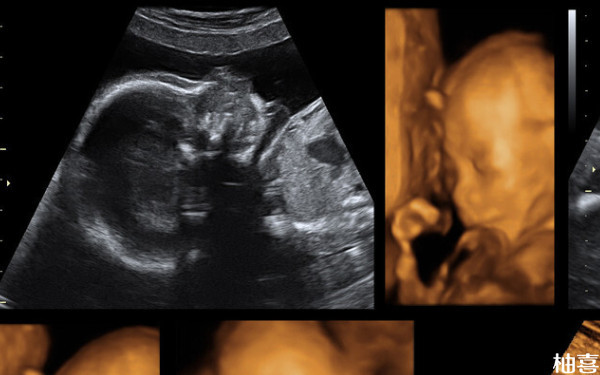

BPD90 HC329 AC345数值正常么?

根据相关了解,BPD90 HC329 AC345数值可能是正常的,该属于一般对应的是孕37-40周,只是要注意,该数据只能作为参考,毕竟孕1-40周b超BPD、HC、AC、FL分别的正常值范围是会随着孕周的增加而增加的,因此每个孕周的正常值是不一样的,因此有需求了解具体情况,建议各位孕妇以自己的检查结果为准。